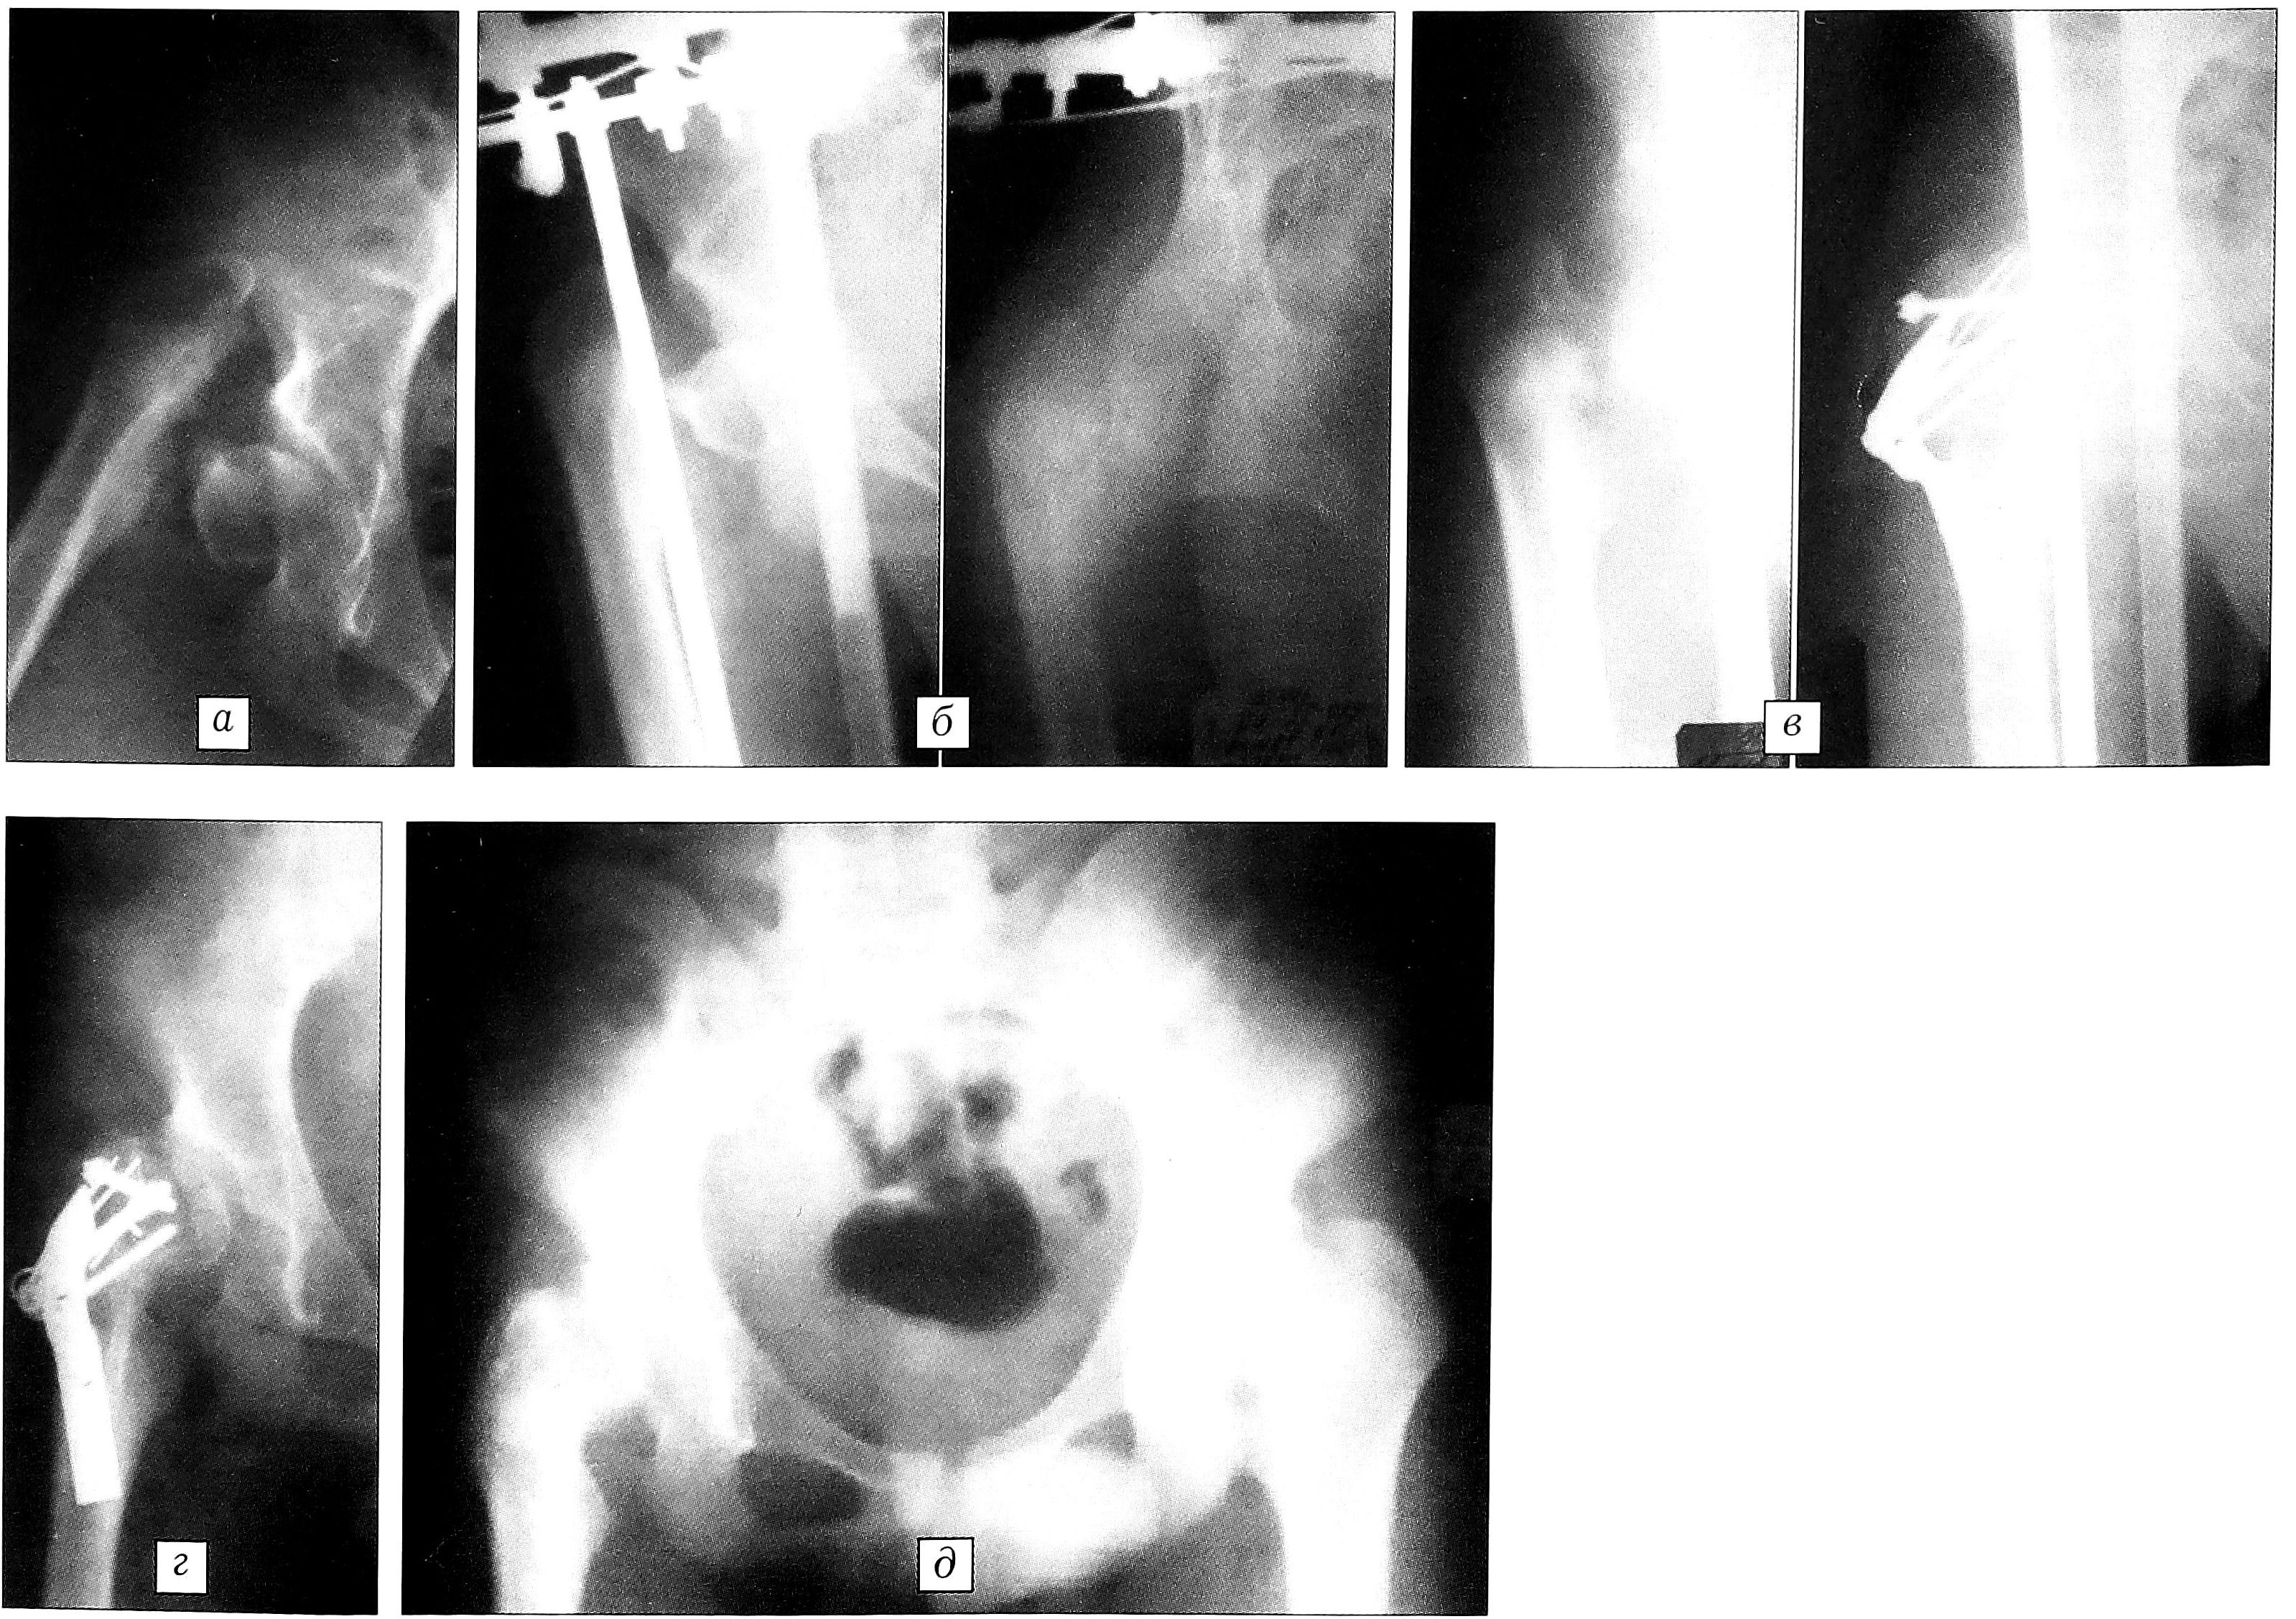

Больной И.,15 лет, поступил в отделение детской ортопедии и травматологии с диагнозом: последствия хронического остеомиелита, деструкция и остеолиз шейки правой бедренной кости с отделением головки, дислокацией и вследствие этого укорочением бедра на 7 см. При осмотре отмечается резкое снижение опороспособности конечности, бедро неопорно. Движения в суставе болезненны, отведение бедра резко ограничено, ротация отсутствует. Выступает вертельная область бедра. Видны множественные грубые рубцы на месте ранее функционировавших свищей по наружной поверхности верхней трети правого бедра и в вертельной зоне. На рентгенограмме: головка с дистрофическими изменениями, находится в вертлужной впадине, развернута, лежит отдельно от бедренной кости, которая смещена кверху, шейка бедра отсутствует полностью. Расстояние от места предполагаемой проекции головки на вертельную область бедра до усеченной торцовой части головки достигает 7 см. Величина диастаза при различных укладках варьирует, однако даже в положении максимального приведения пораженной конечности минимальный диастаз между бедром и головкой превышает 2,5 см по кратчайшему расстоянию (рис. 2, а).

С учетом этих обстоятельств оперативное вмешательство проведено в два этапа. 17.08.00 наложен аппарат Илизарова с базой на подвздошной кости и в нижней трети бедра. Начаты дистракция и дозированное низведение бедра (рис. 2, б). 10.10.00 без снятия аппарата выполнен второй этап операции (рис. 2, в). Наружным доступом из межотломкового пространства удалена фиброзная ткань. Отмечен выраженный остеопороз большого вертела и головки бедренной кости. Головка развернута во впадине, репонирована до костного торцового контакта с медиальной частью вертела. К месту контакта подведен костный трансплантат из апофиза большого вертела на мышечной ножке, подготовлен трансплантат из надкостницы на дистальной мышечной ножке. Произведен остеосинтез головки компрессирующим винтом и спицами вместе с трансплантатом. Частично резецирован нижний сегмент головки. Выполнена удлиненная косая межвертельная остеотомия бедра, медиальный костный шип подведен и внедрен под нижний сегмент головки. При этом место костного контакта с торцовой частью головки снизу оказалось перекрыто остеотомированной частью дистального фрагмента бедра, который в данной ситуации предположительно должен был играть роль дополнительного кровоснабжаемого костного мостика. Фрагменты фиксированы пластиной типа Блаунта, трансплантат на нижней мышечной ножке подведен к месту костного контакта. Рана зашита наглухо, введен трубчатый дренаж для вакуум-аспирации. Аппарат Илизарова не демонтировали с целью разгрузки и декомпрессии на уровне головки бедра в ближайшем послеоперационном периоде.

Через 1 год после операции пластина была удалена (рис. 2, г). Через 2 года на рентгенограмме: костная структура головки восстановлена, форма головки сферическая, определяется полное костное сращение ее с бедром. Имеется деформация вертлужной впадины, латерализация головки (рис. 2, д). Больной результатом лечения доволен, от коррекции тазового компонента отказался. Отведение бедра 70°, наружная и внутренняя ротация соответственно 15 и 10°. Ходит с полной опорой на оперированную ногу, продолжает реабилитацию.

Рис. 2. Рентгенограммы больного И. 15 лет. а — исход хронического рецидивирующего остеомиелита: шейка бедра полностью отсутствует, головка с нарушенной структурой и формой лежит отдельно в вертлужной впадине, бедро дислоцировано кверху; б — на первом этапе лечения: низведение бедра в аппарате Илизарова; в — после выполнения второго этапа реконструктивной операции; г — через 1 год после оперативного лечения: консолидация головки, восстановление целости проксимального отдела бедра; д — через 2 года после оперативного лечения: полное сращение головки с бедром, восстановление костной структуры.